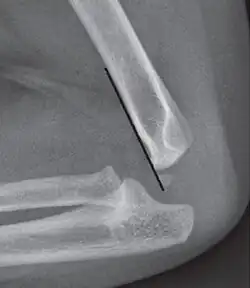

Anterior humeral line - It is a line drawn down along the front of the humerus on the lateral view and it should pass through the middle third of the capitulum of the humerus.[9] If it passes through the anterior third of the capitulum, it indicates the posterior displacement of distal fragment.[8]

Coronoid line - A line drawn along the anterior border of the coronoid process of the ulna should touch the anterior part of the lateral condyle of the humerus. If lateral condyle appears posterior to this line, it indicates the posterior displacement of lateral condyle.[8]